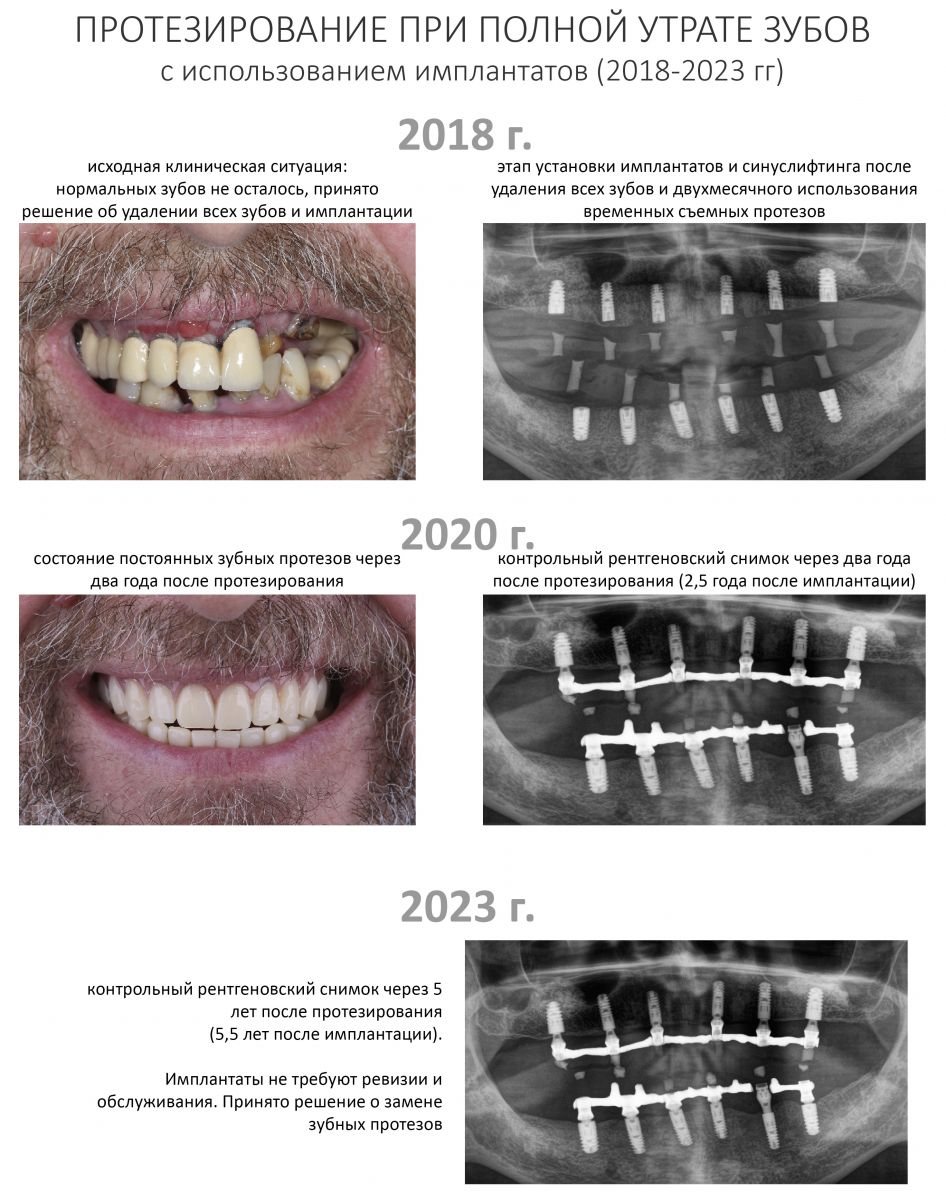

Пациентка того же возраста, что и Елена, начала лечение в нашей клинике около шести лет назад. В течение 2017-2018 гг. мы провели очень большую работу:

В конце 2018 года, сразу после временного протезирования установленных имплантатов на верхней челюсти, пациентка… исчезла. То есть, перестала ходить на приемы. Наши попытки пригласить её на профосмотры и продолжение лечения, замену временных протезов на постоянные или хотя бы на новые временные, не увенчались успехом. Пациентка сказала нам, что очень занята, сейчас ей вообще не до зубов. И что у неё «все нормально», она запишется на продолжение лечения сразу же, как появится время.

Прошло пять лет. Наконец, у Анны (так зовут неуловимую пациентку) появилось время. Но не на продолжение лечения, а для решения возникших стоматологических проблем, которых накопилось немало. Превысив все возможные и невозможные сроки службы временных композитных протезов (которые, кстати, стерлись в ноль, что привело к дисфункции височно-нижнечелюстного сустава), забыв про гигиену полости рта, она свела к нулю всё проведенное ранее лечение и довела установленные имплантаты до состояния, в котором их невозможно нормально протезировать:

Конечно, мы решим эту проблему. В нашей клинике накоплен достаточный опыт лечения периимплантитов и ревизий давно установленных имплантатов. В конце концов, протез можно снова заменить на временный, некоторые имплантаты поменять, а оставшиеся привести всё в порядок.

Однако, кто виноват в возникшей ситуации и кто должен платить за доделки-переделки?

— чем больше размер зубного протеза, тем более уязвимы дентальные имплантаты, и тем более опасным является несоблюдение условий по эксплуатации и уходу. Другими словами, одиночный имплантат с керамической коронкой еще способен пережить пофигистическое отношение, а вот для мостовидной конструкции, типа «всё-на-четырех» или «всё-на-шести», последствия пациентского пофигизма будут катастрофическим. Собственно, мы это наблюдали во втором примере в начале статьи.